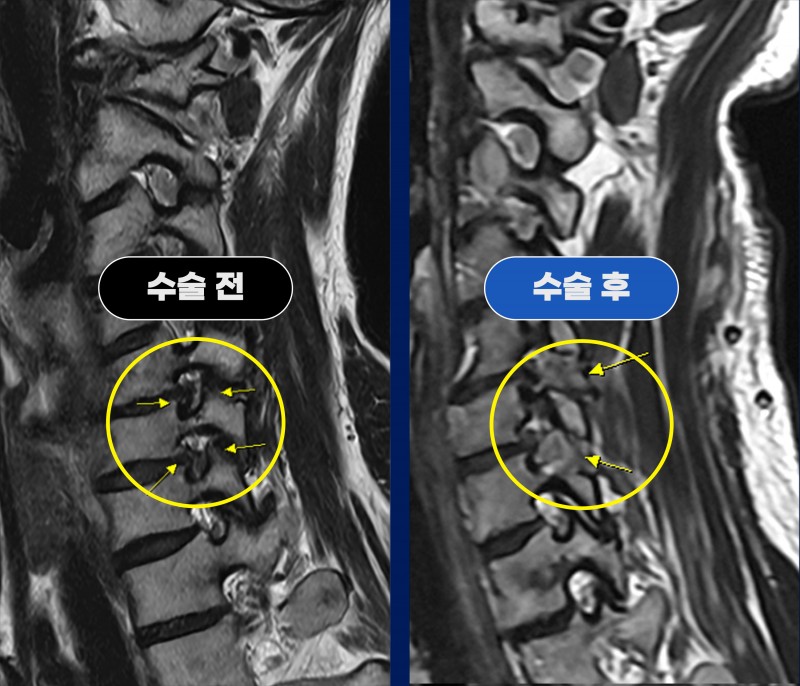

경추 협착증과 급성 목디스크, 후방 내시경 감압술 치료 사례

Before (수술 전)

54세 여성 환자분께서 경추 협착증으로 인한 좌측 팔 저림 증상이 평소에도 있으셨으며,

최근 들어 통증이 급격히 심해지고 팔 힘까지 떨어지는 증상이 발생하여 내원하셨습니다.

타 척추전문병원에서 MRI 검사 후

경추 2마디 전방유합술(ACDF) 을 권유받으셨으나,

목 앞쪽으로 접근하는 수술에 대한 부담감이 크셔서

가능하면 뒤쪽으로 진행하는 수술 방법을 원하셨습니다.

검사 결과

C5/6, C6/7 추간공 협착증

C6/7 급성 디스크 파열

이 함께 확인되었으며,

기존 협착으로 눌려 있던 신경에 디스크 파열이 추가되면서

통증이 급격히 심해진 상태로 판단되었습니다.

■ After (수술 후)

환자분은 양방향 내시경을 이용한 2레벨 후방 감압술 을 시행하였으며,

C6/7 파열된 디스크 제거

C5/6 좁아진 추간공 확장술

을 함께 진행하였습니다.

수술 후 MRI에서

두 레벨 모두 신경이 지나가는 통로가 충분히 넓어졌고

파열된 디스크도 깨끗하게 제거된 것이 확인되었습니다.